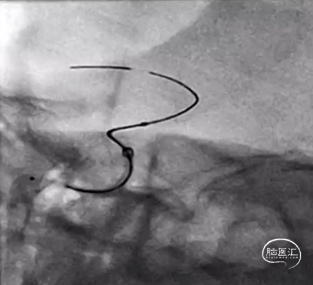

右侧小脑后下动脉瘤Nuva®血流导向密网支架成形术。

全身肝素化,送入长鞘、中间管,在导丝指引下置入TJMC18Plus微导管。

术后造影见支架打开好、贴壁好,动脉瘤内可见造影剂滞留。